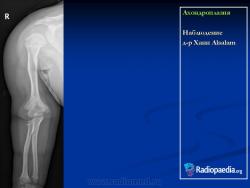

Ахондроплазия

http://radiopaedia.org/images/392220

http://radiopaedia.org/cases/achondroplasia

Ахондроплази́я (диафизарная аплазия, болезнь Парро-Мари, врожденная хондродистрофия) — известное с древности наследственное заболевание человека, проявляющееся в нарушении процессов энхондрального окостенения (вероятно, в результате дефектов окислительного фосфорилирования) на фоне нормальных эпостального и периостального окостенений, что ведет к карликовости за счет недоразвития длинных костей; характеризуется наличием врождённых аномалий, в частности врождённого стеноза позвоночного канала. Наследуется по аутосомно-доминантному типу.